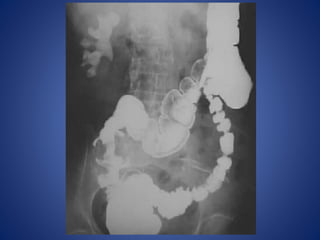

RADIOLOGICAL PICTURE

 Small Bowel Obstruction

- Central distention (GAS)

- Valvulae conniventes

- “Ladder-like dilatation”

- Small diameter

 Large Bowel Obstruction

- Peripheral distention “Picture frame”

- More gross distention

- Haustral indentation & large diameter

In most cases, the abdominal

radiograph will have the

following features:

1. ileated loops of small

bowel proximal to the

obstruction

2. predominantly central

dilated loops

3. dilatation of loops over

3cm

4. valvulae conniventes are

visible

Large Bowel Obstruction